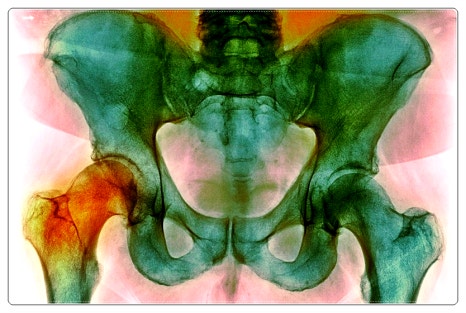

예를 들어 무릎 통증이 발 사용 습관이나

골반의 불균형과 연결되어 있는 경우도 적지 않습니다.

문이 잘 닫히지 않을 때

문짝보다 문틀을 먼저 살펴보는 것과 비슷한 이치라고 보시면 이해가 쉽습니다.